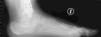

Mala consolidación tipo II: exostosis lateral prominente y artrosis subastragalina (fig. 9). Tratamiento mediante exostectomía lateral, tenólisis de peroneos y artrodesis subastragalina con injerto estructural en bloque (figs. 10 y 11).

Mala consolidación tipo III: exostosis prominente, artrosis subastragalina y mala alineación del retropié mayor a 10°. Tratamiento mediante exostectomía, tenólisis de peroneos, artrodesis subastragalina con injerto en bloque (artrodesis y distracción) además de osteotomía de calcáneo (varizante o valguizante).